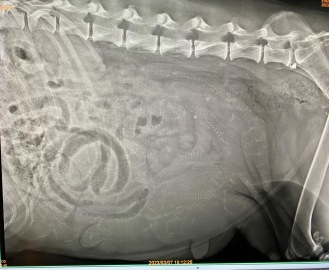

Röntgen med Vilda idag dygn 46 och vi såg 8-9 valpar . Och Vilda hade gått upp i vikt 8,5 kg.

Nu är det lite över 2 veckor kvar....

Åh , hur vi väntar ...

7.3 -23

Dygn 46